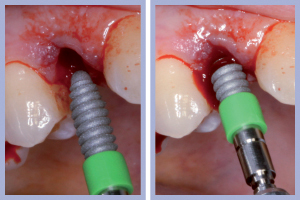

- Figg. 9a, b – Preparazione del sito di destra

- Figg. 10a, b – Preparazione del sito di sinistra

- Figg. 11a, b – Inserimento dell’impianto di destra. Max Stability da 3,75 x 12 mm

- Figg. 12a, b – Impianto di destra inserito

- Figg. 13a, b – Inserimento dell’impianto di sinistra. Max Stability da 3,75 x 12 mm

- Figg. 14a, b – Impianto di sinistra inserito

– Preparazione del sito implantare con tecnica flapless (Figg. 9-10);

– Inserimento implantare (Figg. 11-14);

Una volta determinato, sul versante palatale dell’alveolo, il giusto asse di preparazione, si lavorava fino alla profondità programmata; la sequenza di frese comunemente impiegate per il diametro implantare da posizionare completava la preparazione dell’alveolo chirurgico. Non era richiesto l’uso della fresa svasatrice dal momento che a livello cervicale l’alveolo presentava un diametro maggiore di quello implantare.

Il posizionamento di due impianti Max Stability da 3,75 mm di diametro e 12 mm di lunghezza ha consentito l’ottenimento di una elevata stabilità primaria, essenziale per portare a termine il carico immediato programmato. Nel caso dell’impianto Max Stability, la forma tronco-conica è associata alla presenza di spire molto prominenti che garantiscono un’elevata stabilizzazione anche in osso di qualità scadente.